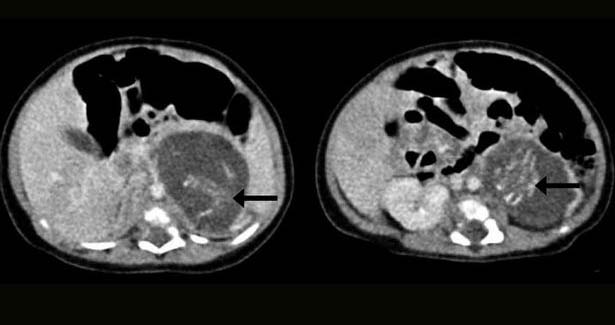

Potrivit Mirror.co.uk, fetusii pe care bebelusul ii purta erau deja formati, aveau maini, picioare, coloana vertebrala si intestine. Unul dintre fetusi cantarea 15 grame, iar celalalt 10 grame. Bebelusul a fost supus unei interventii chirurgicale pentru ca fetusii sa fie indepartati.

Cazul din China este foarte rar, fiind posibil o data la 500.000 de naşteri. Medicii au declarat ca este primul caz de acest gen din cariera lor si ca la nivel mondial s-au inregistrat 200 astfel de cazuri. Cauza acestei anomalii nu este cunoscuta, insa medicii presupun ca ar avea legatura cu avorturile pe care le face o femeie